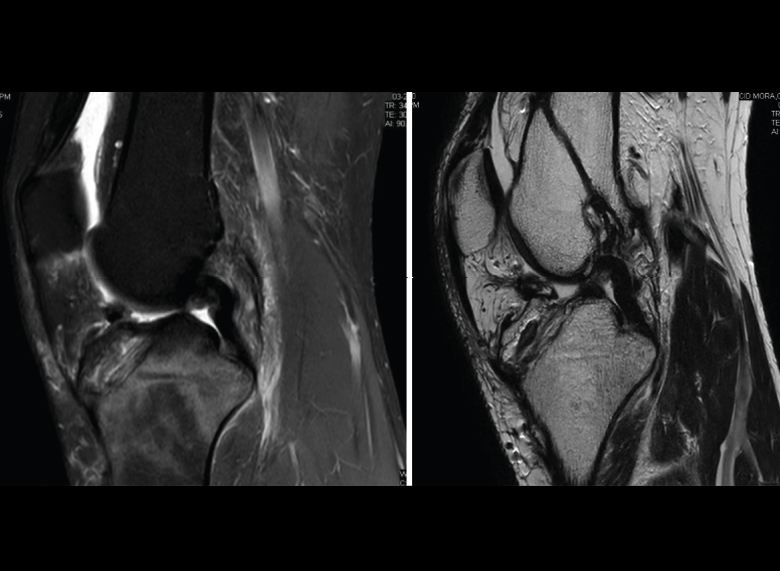

1.1. Meniscos

Figura 30. Corte de secuencia sagital T2 Fat-Sat de resonancia magnética de rodilla: menisco externo normal.

Se identifican como estructuras hipointensas en todas las secuencias, con asta anterior y posterior de morfología triangular.

Figura 31. Corte de secuencia sagital T2 Fat-Sat de resonancia magnética de rodilla: menisco interno normal.

La RM es la técnica de elección en el diagnóstico de la patología meniscal(17)(Figuras 30, 31, 32, 33, 34 y 35).

Figura 32. Corte de secuencia coronal T2 Fat-Sat de resonancia magnética de rodilla: rotura de menisco interno horizontal.

Figura 33. Corte de secuencia sagital T2 Fat-Sat de resonancia magnética de rodilla: menisco interno con cambios mucoides.

Figura 34. Corte de secuencia sagital T2 Fat-Sat de resonancia magnética de rodilla: rotura en asa de cubo desplazada al asta anterior del menisco externo.

Figura 35. Corte de secuencia coronal y sagital de resonancia magnética de rodilla: rotura en asa de cubo del menisco interno con fragmento desplazado al intercóndilo.